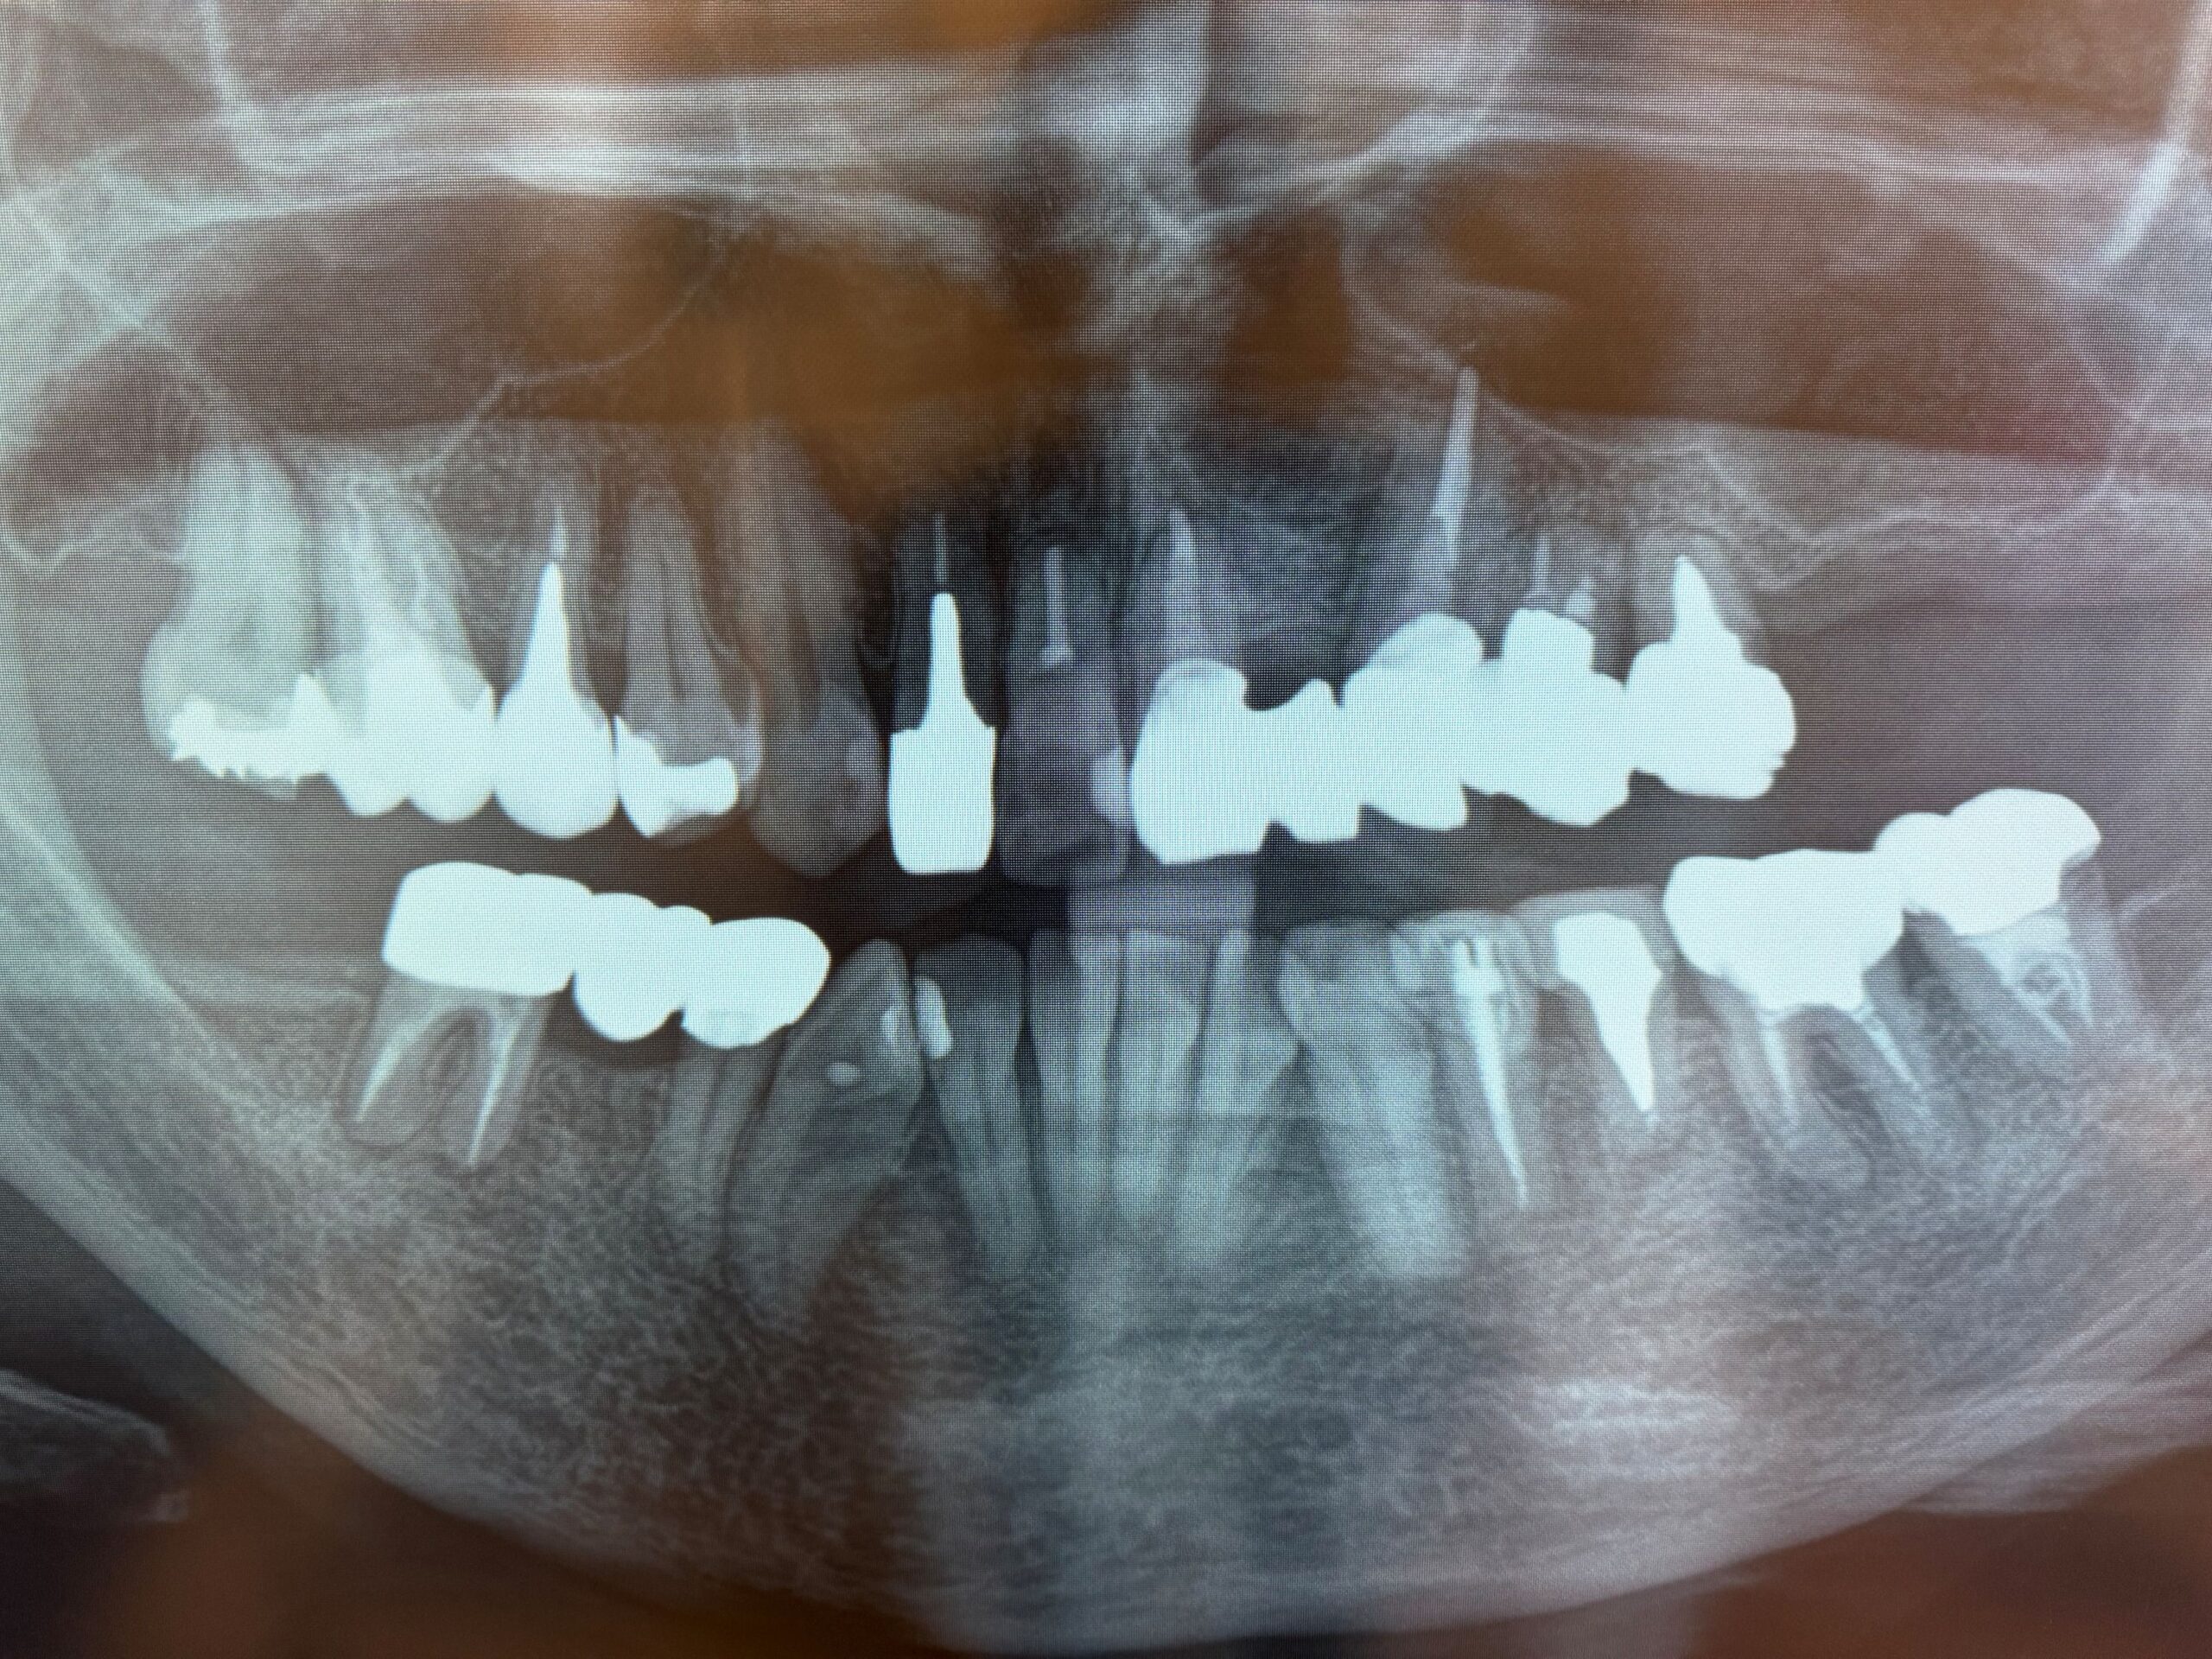

歯根破折の原因を考える

左上6.7番がなくて、入れ歯を使っています。噛みやすいのは、

そうすると右下のブラッジで噛むことになるます。すごい酷使する

おっ。やっぱり。

その結果、歯肉が腫れていると。

ブリッジを外し、土台を外した結果、根が破折していました。

原因は、このヒビです。